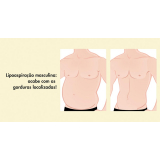

Lipoaspiração a Laser

Você merece a qualidade e comprometimento entregues pela equipe deste consultório médico e se neste momento está à procura de uma equipe que realize lipoaspiração a laser saiba que a FF Cirurgia Plástica disponibiliza de imediato este serviço para você!

Lipoaspiração a laser: atendimento eficiente e com qualidade que você sempre buscou!

Neste consultório médico você encontrará profissionais eficientes e com experiência de excelência. Usufrua de bom atendimento, através dos melhores preços do mercado e de assistência especializada sempre à sua disposição! Leve as suas dúvidas, converse com a equipe da FF Cirurgia Plástica. Contrate bons serviços e sinta-se mais seguro para cuidar da saúde.